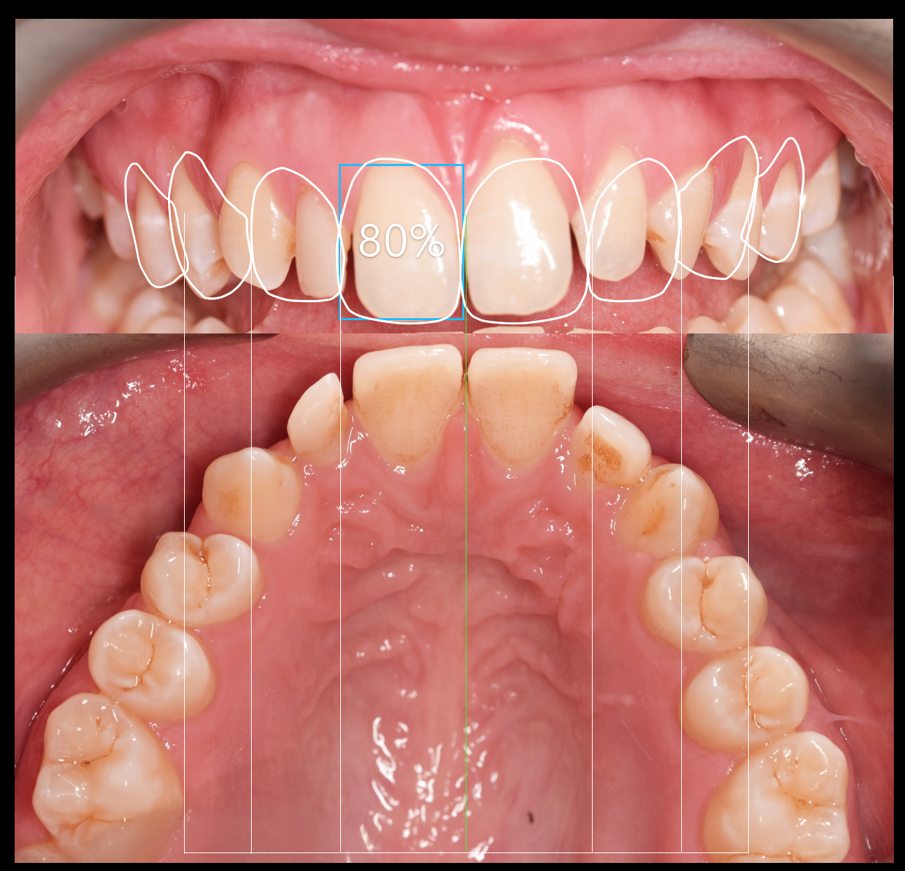

A treatment plan was constructed based on a facially driven smile design, with calibrated images measured against the invisalign clincheck software. The benefit to using a digital system here was to allow for accurate positioning of the anterior teeth for minimal preparation and the ideal restorative outcome. (Figs. 1a-f)

A 7 week invisalign programme allowed for enough movement in the upper arch, while resolving the mild crowing in the lower arch. The final tooth position can be seen in figure 1f.

Post-ortho provisional retention was implemented with removal essix retainers which were used for home whitening of the upper and lower teeth. A final shade of BL3 was achieved, after 10 days of rehydration. In this time the lab created a diagnostic wax up guided by the smile design. A putty matrix was used to transfer the wax up to a trial smile (Fig. 2).